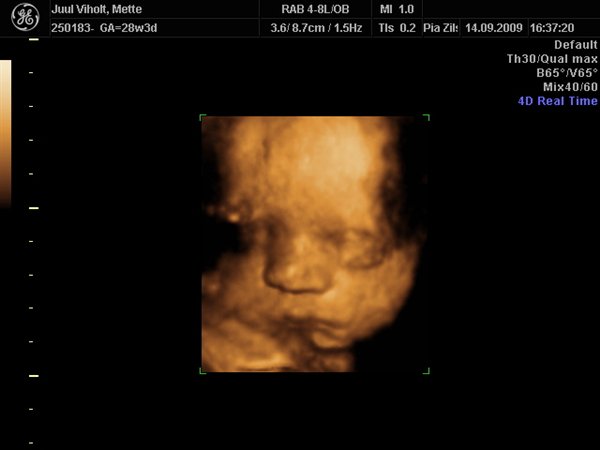

Hun ser dejlig ud, Tutski

Vi gav 1800 kr. for en scanningspakke med en kønsscanning i 17-18 uge og en 3D mellem uge 28-32.

Til 3D scanningen fik i 70 billeder printet OG på Cd, og hele scanningen med lyd på DVD.